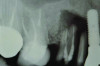

Patient 2: A 63-year-old healthy male patient presented with implant No. 6 exhibiting RPI, having been affected by previously endodontically treated and fractured tooth No. 5 (Figure 3 and Figure 4). The implant had probing depths ranging from 4 mm to 10 mm (Table 1) with the most severe bone loss at the distal aspect of implant No. 6 (Figure 3 and Figure 4).

Fig 3 and Fig 4. Case 2: Initial clinical presentation showing implant No. 6 with RPI, having been impacted by fractured tooth No. 5 (Fig 3); radiograph showing fractured tooth No. 5 with periapical lesion extending to the distal aspect of implant No. 6 (Fig 4).

Figure 3

Fig 4. Case 2: Initial clinical presentation showing implant No. 6 with RPI, having been impacted by fractured tooth No. 5 (Fig 3); radiograph showing fractured tooth No. 5 with periapical lesion extending to the distal aspect of implant No. 6 (Fig 4).

Figure 4